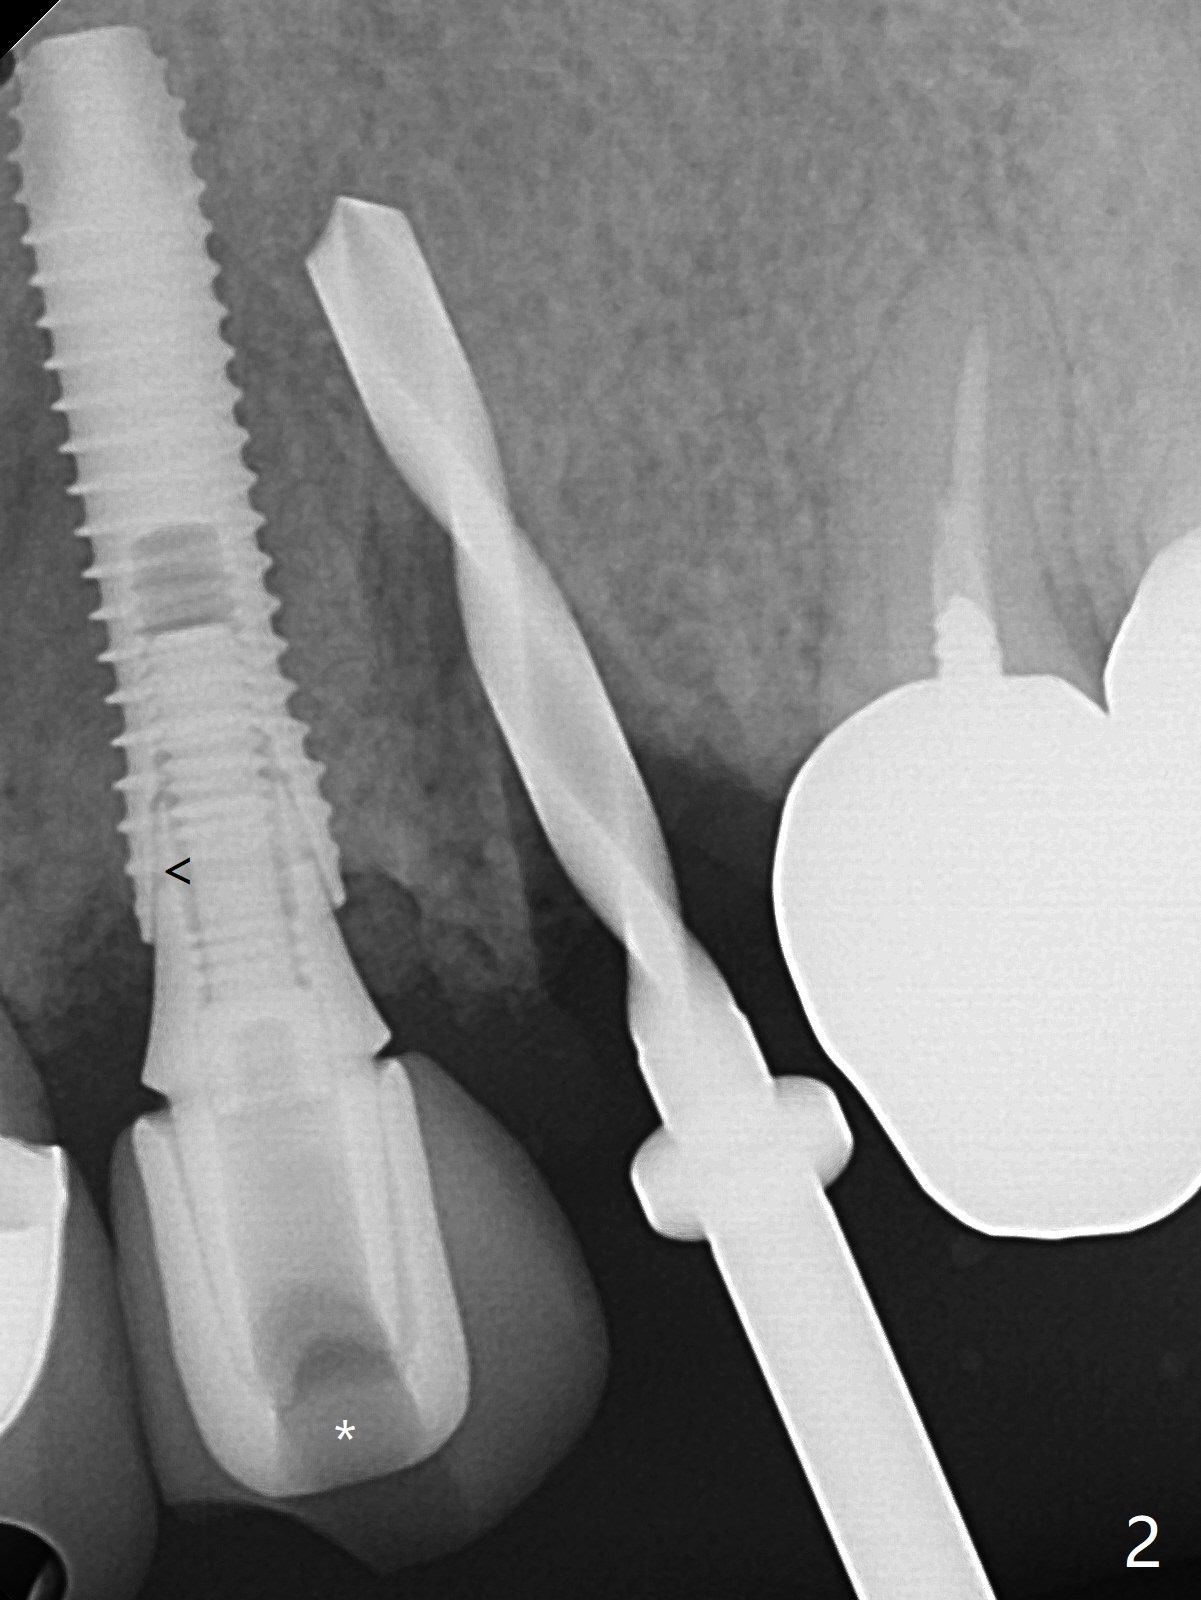

52岁女左上4颊侧牙龈显著肿胀(图一:*(颊侧骨板缺失))伴有瘘道(<),拔除前,在3植牙牙冠切缘舌侧形成开口(图二:*,准备纠正基台不全就位(<);4初步钻洞不正。改变钻头方向后(图三),完成植体放置(图四),并且安置修复基台(4.5x4(2))。磨去3牙冠近中面(图六:*),牙冠和基台反时针旋转(图六:弯箭头),基台完全就位(图四:箭头),调𬌗后,制作4临时牙冠(图六),放置后者前,覆盖半张PRF膜(促进下面粘性骨粉愈合)。图五,六颊侧隆起是因为下面放置许多粘性骨粉。图七是术前CT3D图像(冠状切面),显示颊侧(B),腭侧(P)牙根。拔牙后显示中隔(图八:S),植体植入腭侧窝(图九:绿色),四面骨质包绕,包括中隔;为了修复颊侧骨板,首先放置半张PRF膜(红色)紧贴颊侧骨板腭侧/牙龈,防止骨粉从瘘道流失,然后放置粘性骨粉(图十:粉红色)。术后2.5月3颊侧牙龈仍然红肿(图十一,十二:*),可能与基台袖太短有关(2毫米,图二至四),所以更换袖3毫米的基台(图十三)。术后四个月(牙冠粘固)3颊侧牙龈炎症明显减退(资料没有显示)。术后2.5月4颊侧骨板没有塌陷(图十二,与术后即刻对比(图六))。3基台放置太颊侧,所以在牙冠腭侧制作小的开口(图十四:>),让多余粘固剂流出。取模前3螺丝就拧紧(35Ncm),而4由于有大的开口,粘固后才拧紧(30Ncm)。两个邻牙其中一个可以取出,容易去除另外一个牙冠残余粘固剂。